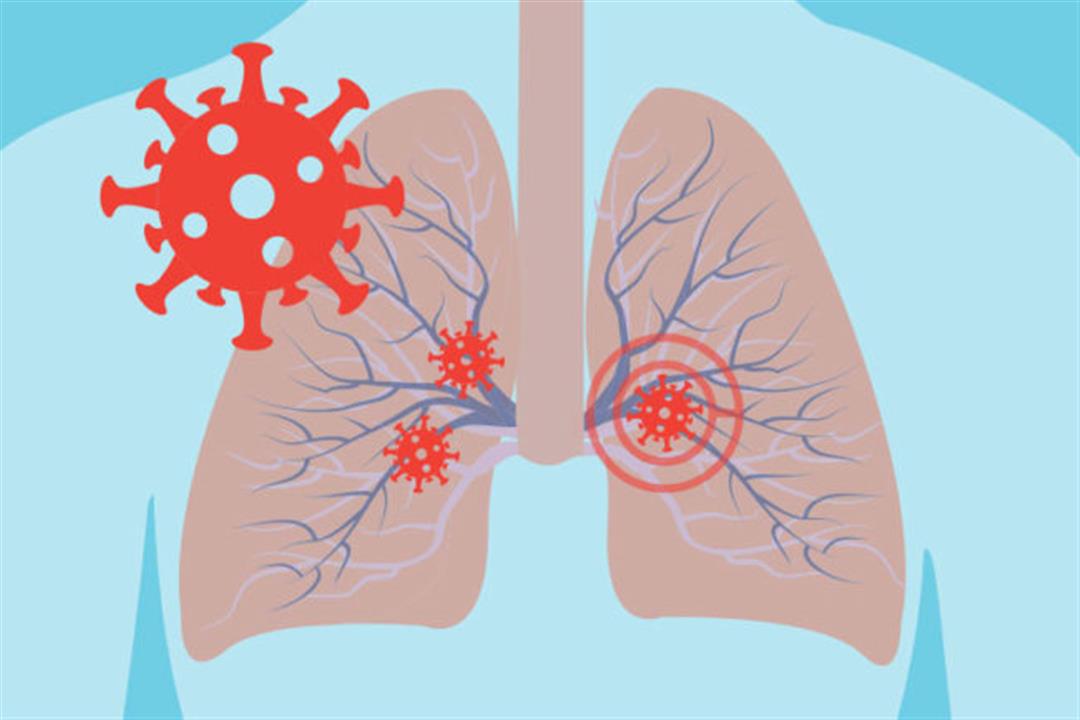

الأشعة السينية تكشف حجم الأضرار التي يسببها فيروس كورونا في الرئة صور اليوم السابع

دراسة مرضى كورونا أكثر عرضة للإصابة بثقب في الرئة الكونسلتو

لالتهاب الرئوي التهاب الرئة Pneumonia مركز طبى سراى القبه Facebook